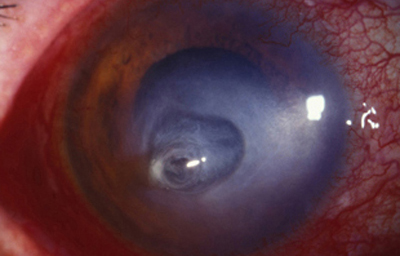

Superficie corneal irregular y grisácea, (Fig. 1, 2) con opácidades granulares en parche y formación de líneas epiteliales elevadas de aspecto granular (Fig. 3), que pueden arborizar dando imágenes de pseudodendritas. Opacidades superficiales satélites. (Figura 4) Inyección ciliar. Ulceración epitelial variante. (Figura 5).

Fig. 4 Focos satélites. Síntomas de meses evolución.